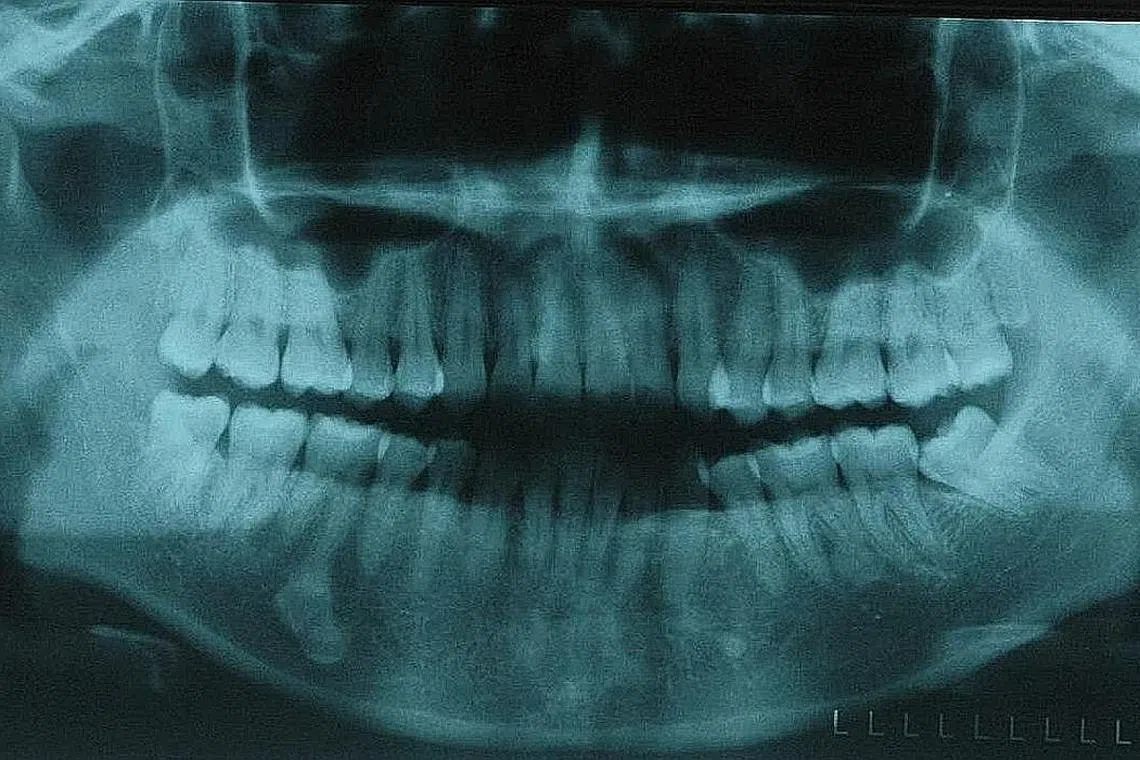

Gigi bongsu atau molar ketiga biasanya tumbuh pada usia antara 17 dengan 25 tahun, meskipun orang ramai biasanya tidak memerlukannya.

Namun adalah lebih biasa bagi gigi bongsu untuk tumbuh sebahagian sahaja, ke tepi, ke arah yang salah atau dalam kedudukan yang menjadikannya sukar dibersihkan.

Ini mendedahkan orang ramai kepada penyakit gusi, karies dan jangkitan, kata Konsultan Kanan dan Ketua Jabatan Oral serta Pembedahan Maksimofacial di Pusat Pergigian Nasional Singapura (NDCS), Profesor Madya Klinikal, Andrew B.G Tay.

Menurutnya, satu kajian yang dijalankan di Singapura pada 2003 mendapati hampir 70 peratus daripada 1,000 pesakit berusia antara 20 dengan 40 tahun mengalami satu masalah gigi bongsu yang terjejas - justeru meletakkan mereka dalam risiko jangkitan selain komplikasi lebih sesius seperti sista (cysts) dan tumor yang boleh sebabkan kerosakan kepada tulang rahang.